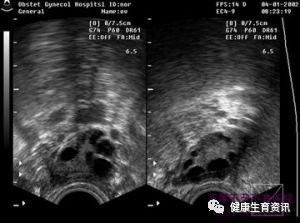

未破裂卵泡黄素化综合征,妇科疾病,是指卵泡成熟但不破裂,卵细胞未排出而原位黄素化,形成黄体并分泌孕激素,体效应器官发生一系列类似排卵周期的改变。临床以月经周期正常,有类似排卵表现但持续不孕为主要特征。是无排卵性月经的一种特殊类型,也是引起的不孕的重要原因之一。.下图为正常排卵:

4、B超连续3个月检测卵泡,有优势卵泡但是无排卵。B超图像分为三型:小卵泡黄素化型(在预计排卵日卵泡体积不变,卵泡直径小于17 mm)、卵泡滞留型(预计排卵日卵泡体积不变,囊泡壁渐渐增厚。2~4 d内卵泡内充满大量强光点,然后逐渐消失)、持续增大型(卵泡直径在25 mm左右或表现为预计排卵日卵泡体积过度增大,直径可达31~50 mm)。卵泡未破裂黄素化囊肿一般于月经来潮时逐渐消失,当于卵巢肿瘤相鉴别,卵巢肿瘤不随月经周期变化。